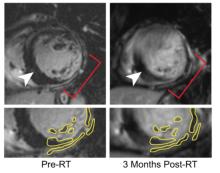

November 17, 2021 — Radiation can be a powerful cancer therapy, but it doesn’t work for everyone. A new study identifies tumor features linked with resistance to radiotherapy, an important advance toward developing individualized cancer treatments.